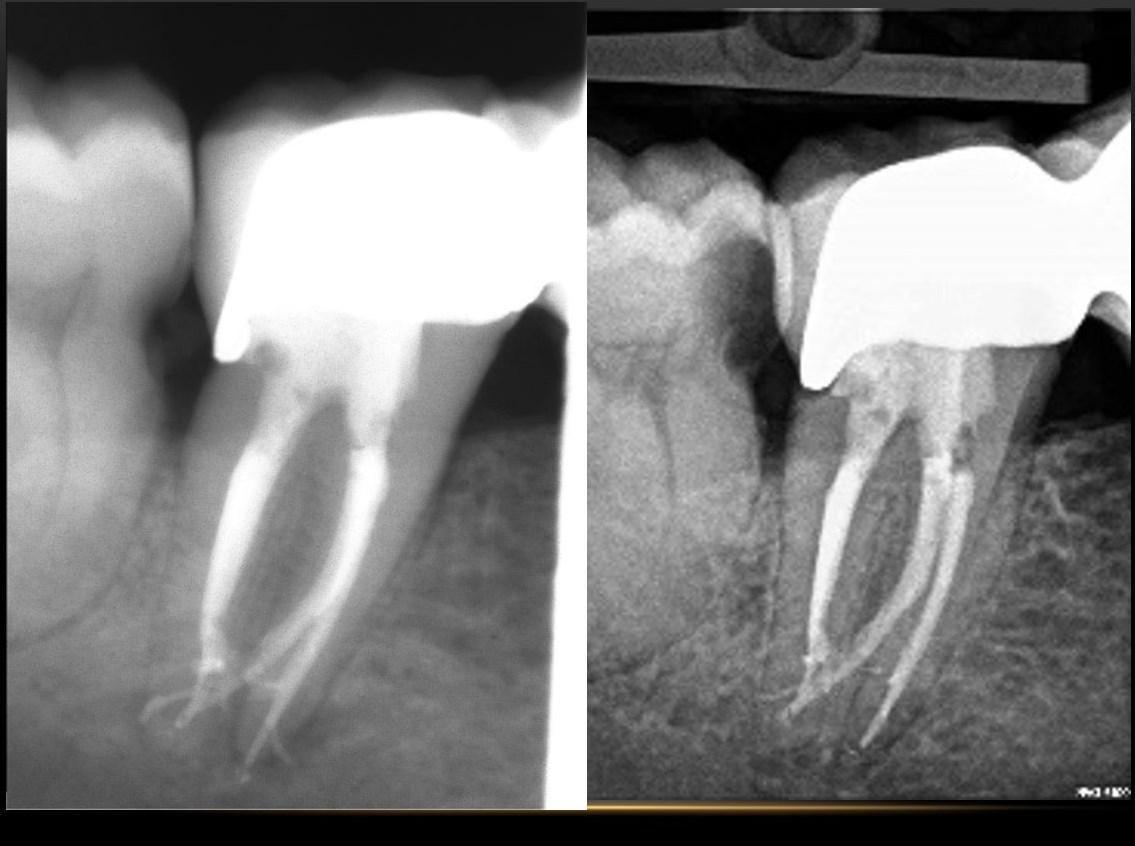

Іригація

Загальна мета  іригації в її науковому і філософському сенсах.

Протоколи іригації в залежності  від  клінічного випадку і діагнозу

Види іригації(  мануальна,  пасивна ультразвукова, звукова, ендоактиватор, Сонік, лазерна активація)

Порівняння  цих видів іригації  в залежності від анатомічних умов

Порівняння успішності лікування в залежності від  виду іригації.

Рекомендації щодо вибору  іригаційної методики при різних діаметрах  і радіусах кривизни кореневого каналу.